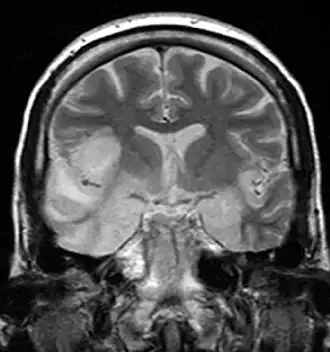

Компьютерная и магнитно-резонансная томография. Также важную роль в диагностике энцефалита играет компьютерная и магнитно-резонансная томография. Они позволяют увидеть очаги поражения в мозгу. Для поиска изменений при энцефалите более информативны результаты магнитно-резонансной томографии. Хотя в начале заболевания изменения на томограммах могут быть незаметны[27].